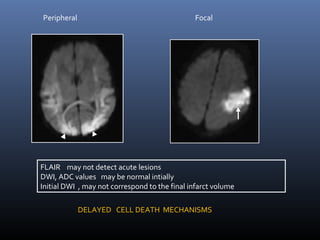

Neonatal hypoxia - findings

Central- Basal ganglia, Ventrolateral thalami, Brainstem

Peripheral-Peripheral cortex, adjacent whitematter

Peripheral Focal

FLAIR may not detect acute lesions

DWI, ADC values may be normal intially

Initial DWI , may not correspond to the final infarct volume

DELAYED CELL DEATH MECHANISMS